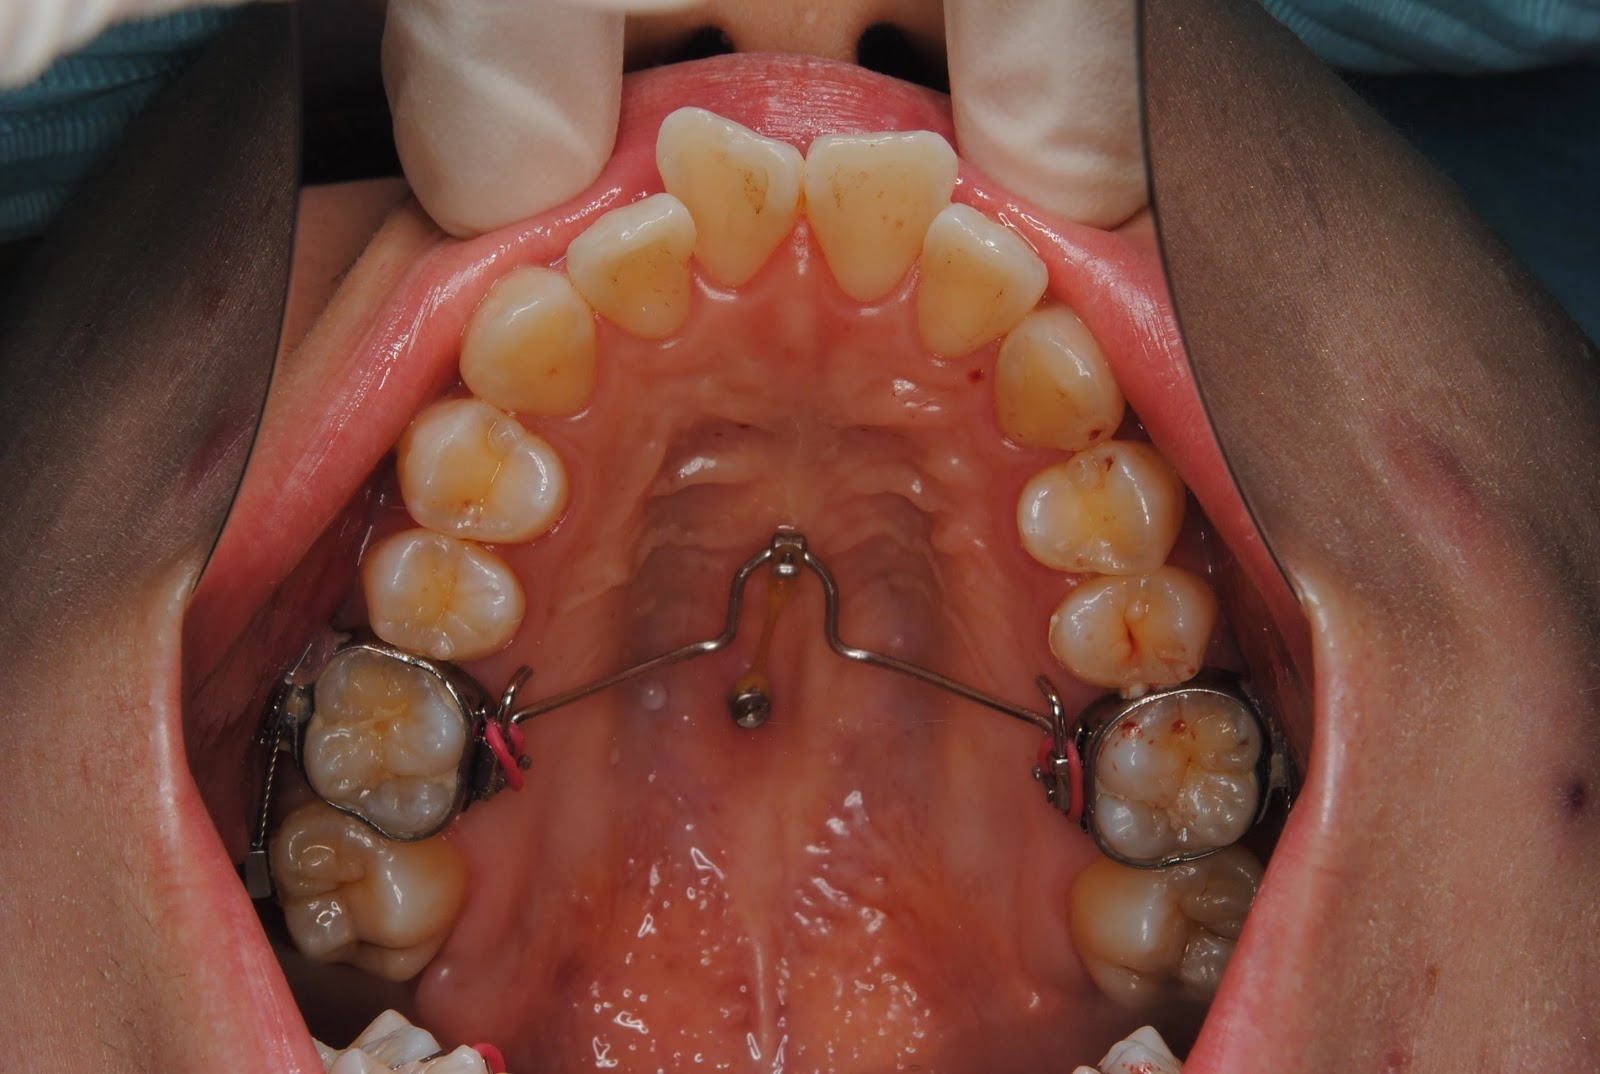

THE METHOD OF PALATAL MINISCREW WITH TRANSPALATALBAR FOR MOLARS

THE METHOD OF PALATAL MINISCREW WITH TRANSPALATALBAR FOR MOLARS Palatal Bar Dental Definition The term palatal surface is used for surfaces of maxillary teeth (both anterior and posterior teeth). Intimate contact between the connector and the supporting tissue adds much to the support, stability, and retention of the denture. The transpalatal arch (tpa) is a stainless steel wire connecting the maxillary molars during fixed appliance orthodontic treatment to assist with anchorage reinforcement. Labial. Palatal Bar Dental Definition.